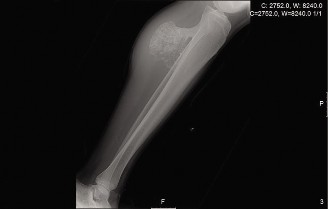

Diagnostic workup primarily relies on plain radiographs, which typically reveal a well-defined, lucent intramedullary lesion with punctate or ring-and-arc calcifications, endosteal scalloping, and cortical thinning. Periosteal reaction is usually absent unless a pathologic fracture has occurred. Magnetic Resonance Imaging (MRI) can provide further characterization, demonstrating the cartilaginous matrix with high T2 signal intensity and characteristic lobular morphology, aiding in differentiation from other lesions and assessing the extent of cortical involvement. Computed Tomography (CT) may be useful for intricate surgical planning or when assessing complex cortical defects or subtle matrix calcifications. Biopsy (incisional or excisional) is reserved for cases where the diagnosis remains uncertain, or there is clinical and radiological suspicion of malignant transformation (e.g., rapidly enlarging lesion, significant pain, cortical destruction, aggressive periosteal reaction).